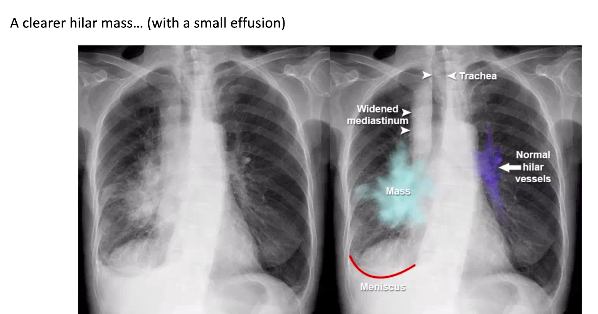

3. Hilar Mass

- Because can cause actelectasis which is what the white mass is